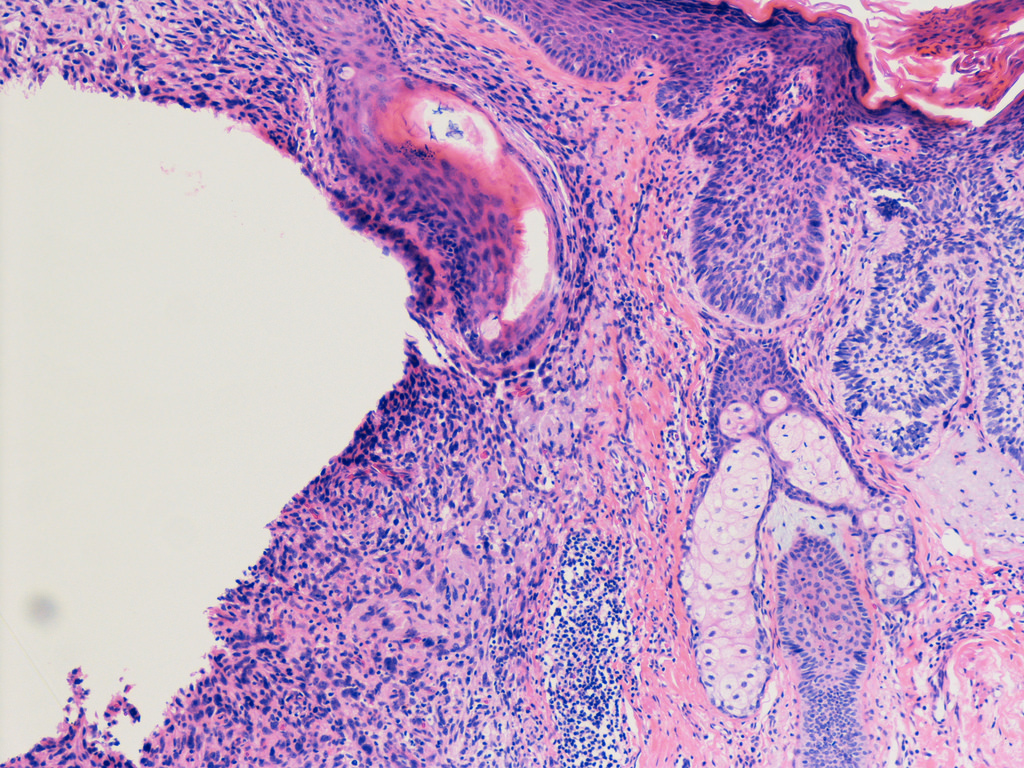

Every biological function – from extracting energy from food to healing a wound – results from activity in different combinations of genes. Cancers hijack the genes that enable people to grow to adulthood and that protect the body from the immune system. Researchers dub these the “hallmarks of cancer.” This so-called gene dysregulation enables a tumor to grow uncontrollably and form metastases in distant organs from the original tumor site.

Researchers are actively using these public data to find the set of gene alterations that are responsible for each tumor type. But this problem is not as simple is identifying a single dysregulated gene in each tumor. Hundreds, if not thousands, of the 20,000 genes in the human genome are dysregulated in cancer. The group of dysregulated genes varies in each patient’s tumor, with smaller sets of commonly reused genes enabling each cancer hallmark.